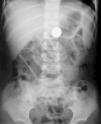

Llega a nuestro servicio de urgencias una niña de 3 años de edad, 3 h después de la ingestión accidental de un cuerpo extraño de plomo. Los padres refieren que el objeto es una pieza de plomo de uso habitual en pesca (plomada de pesca), de forma semiesférica y de aproximadamente 1 x 2 cm de tamaño. A la exploración física, la niña presenta buen estado general, sin sintomatología asociada, siendo sus constantes vitales normales. Se realiza radiografía de abdomen donde se visualiza cuerpo extraño de densidad metálica alojado en antro gástrico (fig. 1). Se obtiene acceso venoso periférico y se retira muestra sanguínea para hematimetría, bioquímica y determinación de valores de plomo en sangre. Inmediatamente se administra inhibidor de bomba de protones (omeprazol) y se traslada a quirófano para la retirada endoscópica del mismo. En quirófano y bajo anestesia general, se logra la retirada del cuerpo extraño, habiendo transcurrido 6 h desde la ingesta. El objeto extraído se corresponde con una plomada de pesca de forma semiesférica con 2 cm de diámetro y 0,5 cm de espesor máximo (fig. 2). La paciente ingresa en planta para vigilancia evolutiva y monitorización seriada de datos de toxicidad aguda y valores sanguíneos de plomo. Las muestras analíticas obtenidas en el momento de la canalización venosa, antes de la extracción del cuerpo extraño y previamente al inicio del tratamiento específico reflejaban un nivel de plomo en sangre de 43,6 μg/dl, siendo el resto de los parámetros analizados normales. Transcurridas 48 h la plumbemia era de 24,7 μg/dl, y a los 7 días de 23 μg/dl. El resto de estudios analíticos seriados de hematimetría, ionograma, metabolismo de hierro y cinc fueron en todo momento normales. A los 5 días, la paciente fue dada de alta, no habiendo presentado en ningún momento datos clínicos o analíticos de toxicidad aguda por plomo, al margen de la elevación de los valores séricos del metal. Transcurridos 3 meses, los niveles de plomo en sangre eran de 6,3 μg/dl. Después de 12 meses de seguimiento evolutivo, la niña continua asintomática, con controles de laboratorio y concentraciones séricas de plomo dentro de la normalidad.

Figura 1. Radiografía simple anteroposterior de abdomen obtenida al ingreso, donde se observa una imagen radioopaca alojada en antro gástrico.